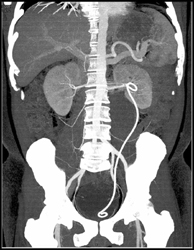

Bladder Cancer With Hemorrhage